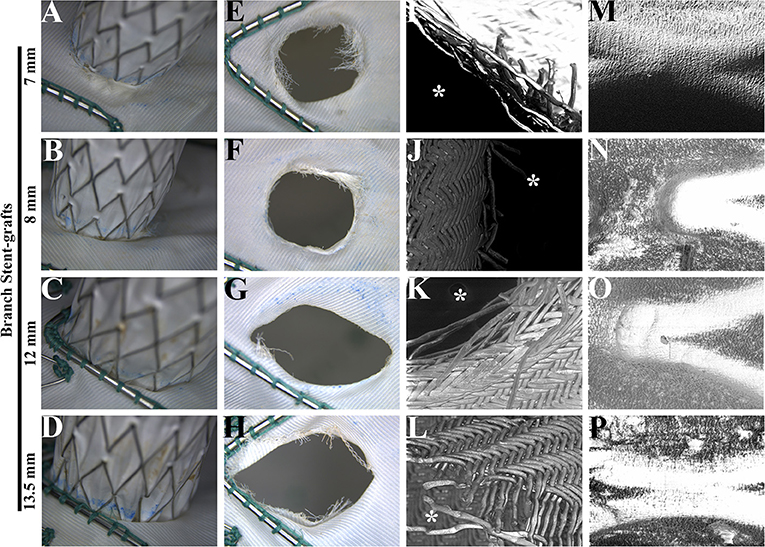

After a 5-year simulated cardiac cycle, the structures of the main and branch stents were stable under light microscopy (Figures 4A–D). The fabrics around holes in each group were basically undamaged and remained connected under the light microscopy (Figures 4E–H). Figures 4I–L showed the SEM observation of fabrics around holes of each group, in which the organization was relatively tight. The membrane and metal structures were intact in the branch stents under the observation of SEM (Figures 4M–P).

Figure 4. Morphological analysis of main and branch stent grafts after a fatigue test. (A–D) The connections of main and branch stent grafts were estimated by light microscopy. (E–H) The fabrics around the fenestrations on the main stent grafts were estimated by light microscopy. (I–L) The fabrics around the fenestrations on the main stent grafts were estimated by scanning electron microscopy. The magnification was 100×. *, the inner side of fenestrations. (M–P) The membrane and metal structures of branch stent grafts were examined by scanning electron microscopy. The magnification was 100×.